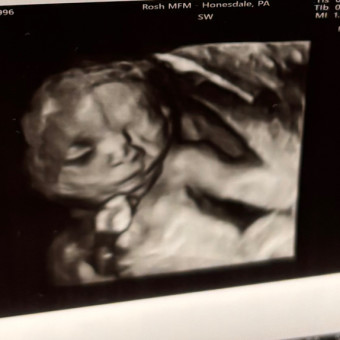

Victoria Angotti’s Baby Registry

Victoria & Joseph Angotti

Carbondale, PA

July 25, 2025

Baby Angotti #3 coming soon!